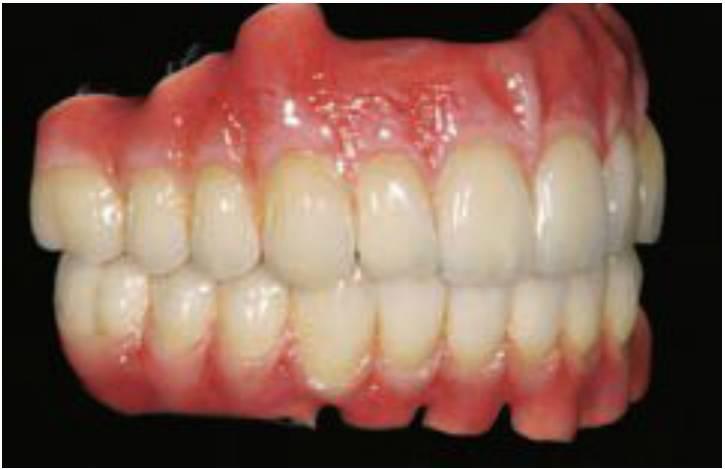

Un método alternativo para fabricar prótesis fijas en situaciones de AEO de 15 mm o más son las dentaduras completas fijas o híbridas, con una estructura metálica más pequeña, dientes de resina y resina acrílica uniendo todos estos elementos (fig. 6-32).

La estructura metálica reducida, comparada con la prótesis fija porcelana a metal, exhibe menores cambios dimensionales y se fijará con mayor ajuste a los pilares, lo que es muy importante para las restauraciones retenidas por tomillos. Es más barata su fabricación que la de la prótesis fija porcelana a metal, es bastante estética (dientes de resina prefabricados), se restituye fácilmente la apariencia de los dientes y de los tejidos blandos y es más fácil de reparar en caso de fractura. Como la resina actúa de intermediaria entre los dientes y la estructura metálica, la fuerza de impacto durante la carga oclusal dinámica también puede verse reducida. Por ello, a menudo, se indica este tipo de prótesis fija para la rehabilitación con implantes en casos de un gran EAO. En ocasiones, el laboratorio diseña áreas interproximales infracontorneadas en ciertas restauraciones para ayudar a la higiene oral y se denominan restauraciones «de agua a presión». Este es un método excelente en la mandíbula; sin embargo, origina empaquetamiento de comida, afecta a los patrones de flujo de aire y puede ocasionar problemas de habla en la parte anterior del maxilar.